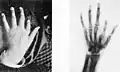

Jeden z prvních snímků s využitím rentgenového záření; publikován r. 1896 v díle Nouvelle iconographie de la Salpétrière Vlevo deformovaná ruka, vpravo stejná ruka pod rtg paprsky. -